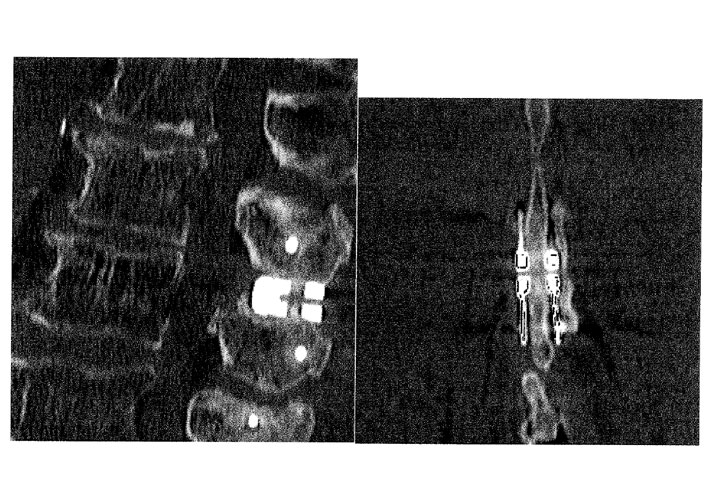

Tuttavia nell’esperienza del nostro studio di Neurochirurgia abbiamo potuto constatare che, grazie ad una diagnosi accurata e specifica, è possibile trattare chirurgicamente la stenosi del canale vertebrale lombare con successo, per giunta ricorrendo a modalità non invasive, anche nei pazienti più anziani. Il caso di studio qui riportato lo dimostra.